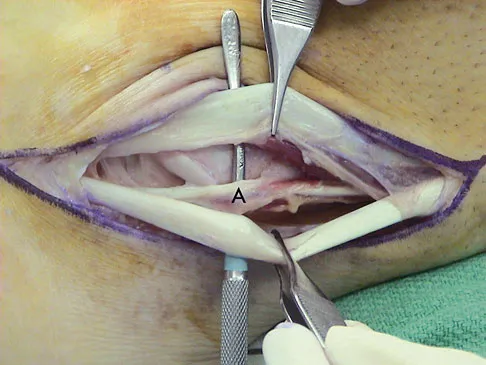

A 35-year-old man is seen for evaluation of his left ankle following multiple previous ankle sprains and frequent episodes of the ankle giving way. Examination reveals marked laxity about the lateral ankle with associated tenderness along the peroneal tendons. Physical therapy, anti-inflammatory drugs, and supportive bracing have failed to provide relief. An MRI scan shows peroneal tenosynovitis and a possible tear. He elects to undergo a peroneal tendon repair and lateral ligament reconstruction. Which of the following best describes the structure labeled "A" in Figure 45?

Correct Answer: Peroneus quartus

The structure labeled "A" is a peroneus quartus, a supernumary muscle arising most commonly from the peroneus brevis. The presence of peroneus quartus is not uncommon, with an incidence of up to 21%, and is associated with lateral ankle pain and peroneal tendon symptoms, theoretically as a result of mass effect within the peroneal tendon sheath. Zammit J, Singh D: The peroneus quartus muscle: Anatomy and clinical relevance. J Bone Joint Surg Br 2003;85:1134-1137.

Sobel M, Levy ME, Bohne WH: Congenital variations of the peroneus quartus muscle: An anatomic study. Foot Ankle 1990;11:81-89.